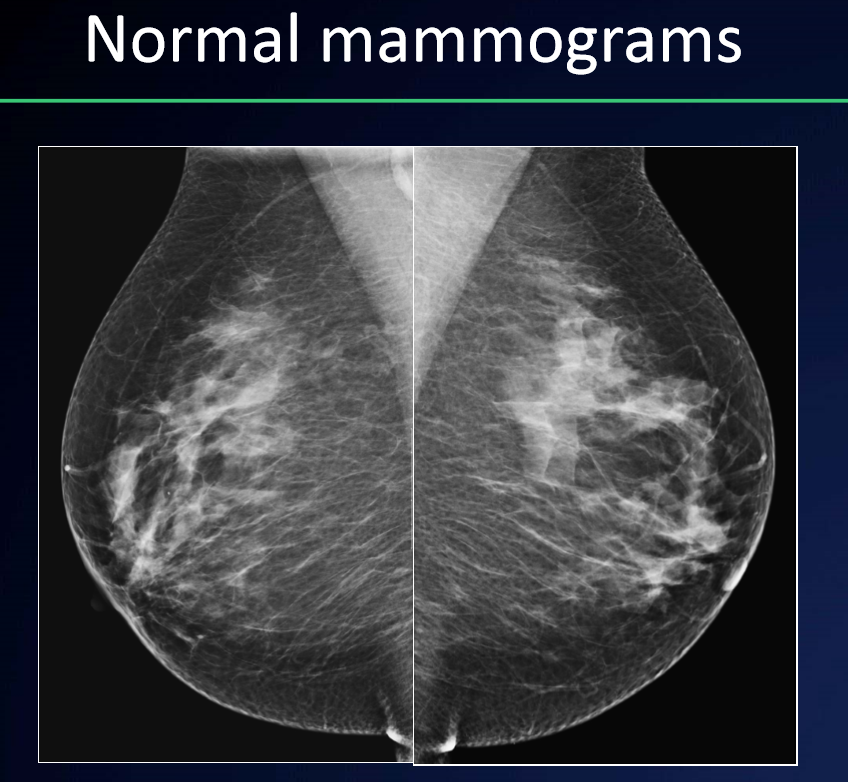

What is the appearance of tissues on XRM?

A

• Fat tissue = low density (darker)

• Glandular tissue = higher density (whiter)

• Calcifications = bright white

• Lymph nodes: oval/horseshoe, fatty hilum